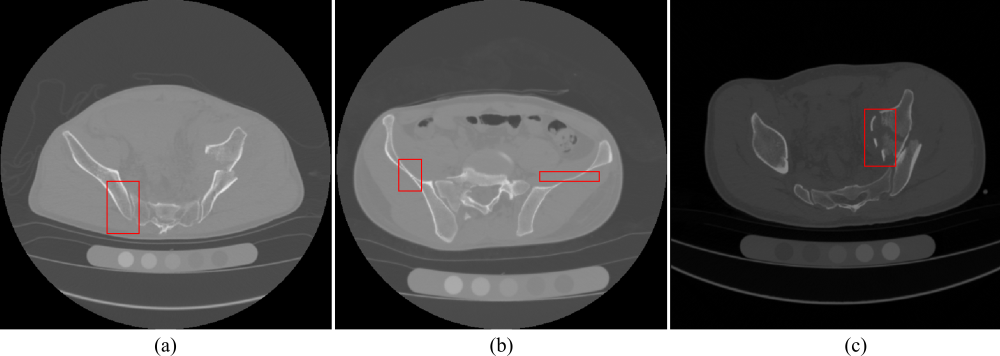

Figure 1: Illustration of bone CT slices from three subjects. It can be observed that due to the inherent anatomical characteristics of the bone structures (the adjacent region of multi-bones in (a) and the narrow and thin regions in (b)), and the various types of fractures in (c), the automated segmentation remains challenging.

Although lots of medical image segmentation methods have been proposed and further employed in various anatomical structures including brain [2], breast [3], abdomen [4], prostate [5] and so on, accurate fracture segmentation in CT scans is still very challenging, as shown in Fig. 1. First of all, the inherent anatomical characteristics of the bone pose difficulties in accurate segmentation. The boundaries of bone structures might not easy to be delineated in the adjacent region of multi-bones (see Fig. 1(a)), and the narrow and thin regions (see Fig. 1(b)). Secondly, fractures have large differences in position and morphology. Moreover, fractures frequently expose cancellous bone, which shares similar intensity to surrounding soft tissue (see Fig. 1(c)), and therefore resulting in challenges in fracture segmentation.